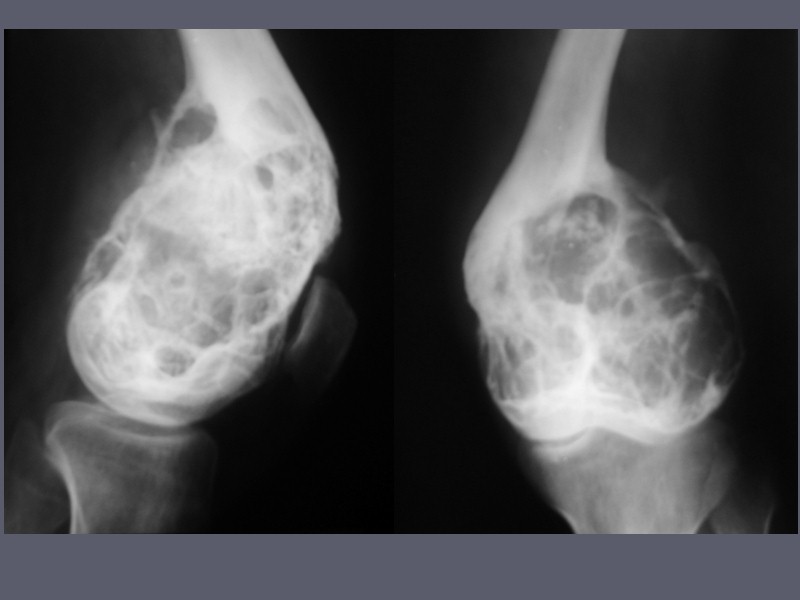

Рентгеновские снимки доброкачественных опухолей костей